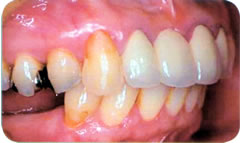

また、上部構造(人工の歯)もセラミック等でできていますので、審美的にも大変美しい仕上がりとなり、乳歯・永久歯に次ぐ「第3の歯」とも呼ばれています。

歯を製作するためにお口の中の型を取ります。製作した人工歯をアバットメント(支台部)に装着して完成です。